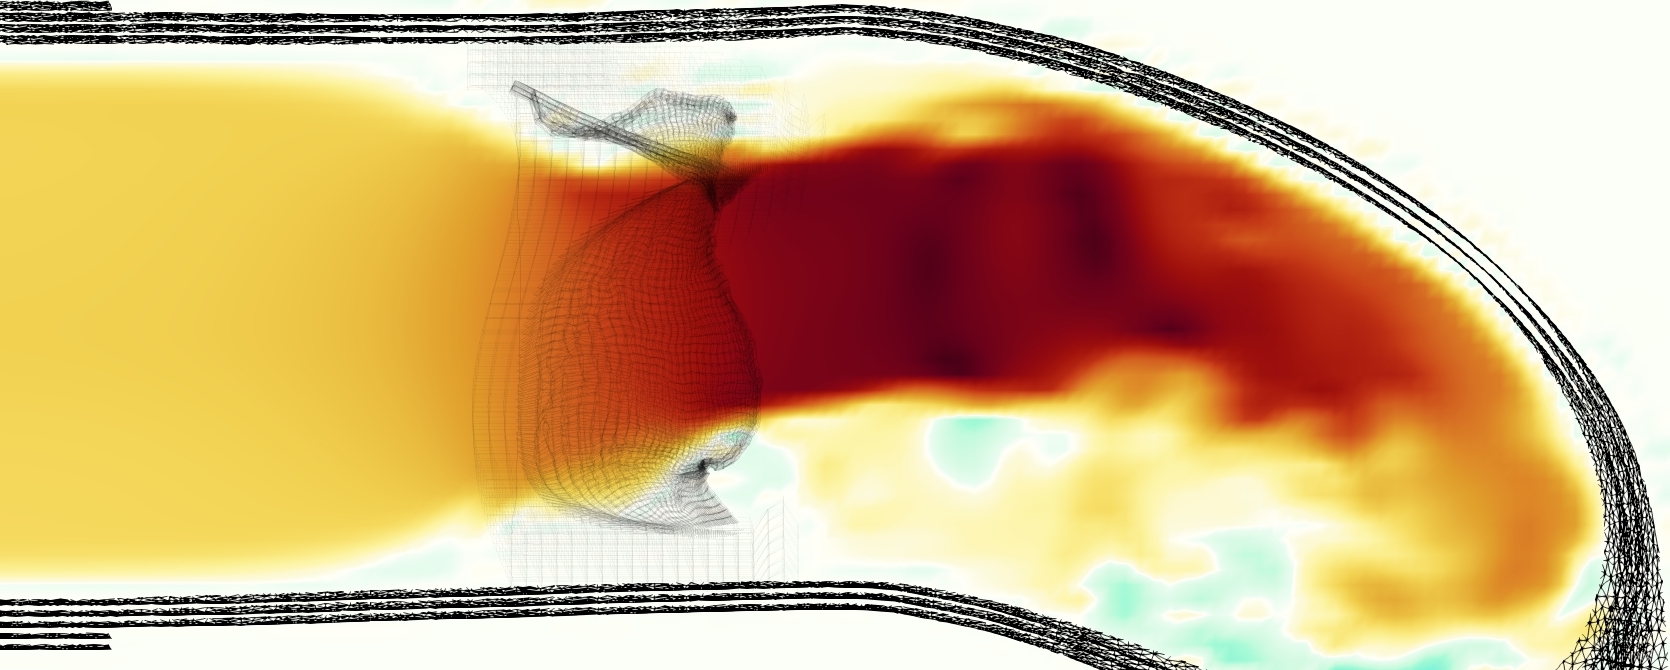

The emergent hemodynamics showed excellent qualitative agreement with experiments. Slice views of the axial component of fluid velocity ( component) in the sagittal plane that cuts through the center of the vessel, parallel to the flow direction, are shown in Figure 5. The flow in both the simulation and the experiment began to accelerate at the same time, with a jet forming through the open valve leaflets. The velocity, angle, and shape of the jet agreed well between the two cases during systole. The simulation captured the slight upward angle of the jet, which was not fully centered in the vessel. It also matched the location where the jet impacts the wall and the slower speed of the jet as it turns with the MPA downstream. As the flow decelerated, the fluid along the interior curve of the vessel reversed first while forward flow persisted where the jet was strongest, as seen in both the simulation and experimental results.

In both the experiment and the simulation, a separation region of reverse flow developed along the interior curve of the vessel under the core jet through the valve. The reverse flow began to develop at the same time in the cardiac cycle and grows throughout systole. The simulation lacked reversed flow in the entire region where reversed flow was present in the experiment, but this region developed some flow separation and had much slower flow than elsewhere in the vessel. Thus, the simulation captured that this is a distinct region from the core jet through the valve opening. There was a smaller amount of slower and slightly reversed flow along the outer curve of the vessel, close to the valve annulus and scaffold support. This region was well-matched between the experiment and the simulation.

Slice views of the (axial) component of fluid velocity in the axial plane, orthogonal to the flow direction, show that the simulation replicated the development of the jet over the cardiac cycle. At each phase, the simulation matched the forward speed of the core of the jet and the locations of reverse flow back towards the valve annulus. While there are some differences in the shape of the jet at certain phases and locations, the simulation clearly produced the general dynamics of the cardiac cycle that are seen in the experiment.

A comparison between the phase-averaged velocity resampled onto the MRI grid, the phase-averaged velocity without resampling, the instantaneous flow field without resampling and the MRI velocity field is shown in Figure 8. The coarser resolution is visible as a “stair-stepping” or “pixelated” effect on the phase-averaged resampled velocity, whereas the edges of the jet are more smooth in the phase-averaged velocity with no resampling. Otherwise, the resampled velocity appears qualitatively similar to the phase-averaged velocity with no resampling. Fine scale features were present in the instantaneous field that were lost in the phase-averaging and resampling process. There was more variation in the local velocity of the center of the jet and local areas of high velocity at the edges of the jet that suggested vortices. Vortical structures adjacent to the jet and in the areas of reversed flow were apparent. These comparisons suggest that 4D flow MRI data may lose substantial fine-scale flow features in the flow field via phase-averaging.

The simulated velocity fields showed excellent qualitative agreement with the experimental velocity. Many features of the flow that were present in the experimental measurements also appeared in the simulations, including a large jet which angled up downstream of the valve and the appearance of a triangle-like shape in the jet. A recirculation zone appeared downstream, though the precise region of recirculation showed only some agreement at some points in time. We prescribed the experimentally measured pressures (subject to minor processing as described in Section 3.3), and the emergent flow rates matched those of the experiments.